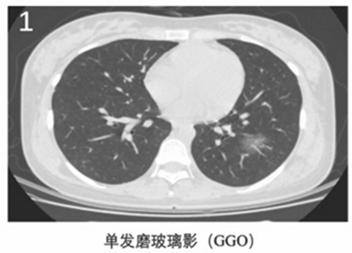

作者指出,2019新型冠状病毒肺炎有以下6个典型的CT影像学征像(图1~6):

(1)单发磨玻璃阴影(GGO);